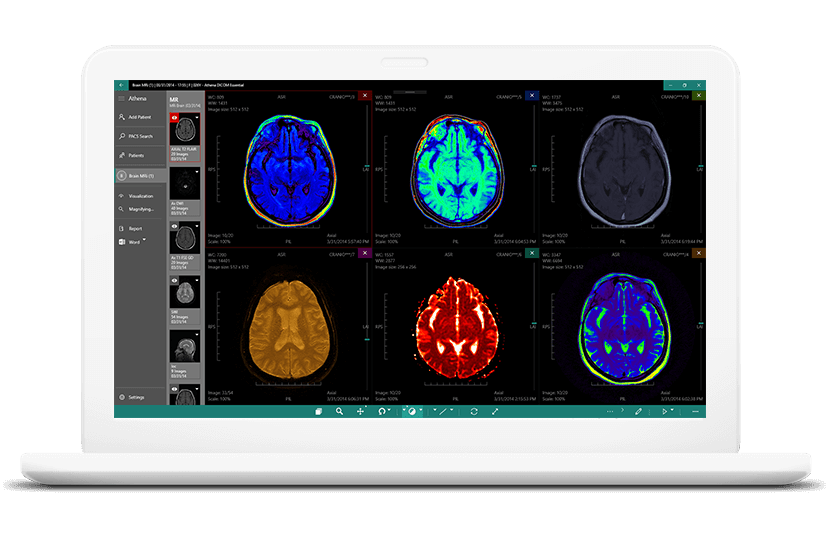

Лазерная камера для печати медицинских изображений на пленке стандарт dicom